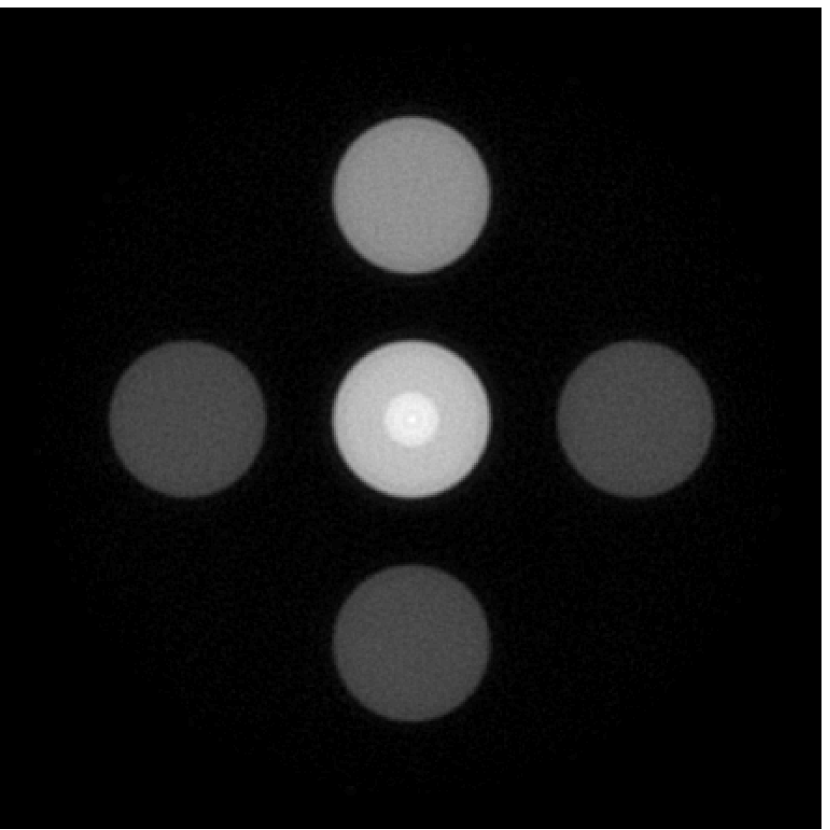

The numerical phantom shown in Figure 1(a) was employed. The phantom had a support area of mm2 and contained six uniform disks that were assigned different values of absorbed optical energy density.

A 2D circular measurement geometry was employed. transducers were evenly distributed on a ring of radius mm that enclosed the phantom. The SOS was assumed to be constant and set at mm/s. Since the simulated data were formed by use of the C-D imaging model in Eqn. (2), no inverse crime was committed. The components of this vector corresponded to equally spaced temporal samples over the interval s. Subsequently, the noiseless voltage vector was obtained by convolving the pressure data with EIR-1 in Figure 1(b).

The reconstruction region ( mm2) was represented by pixels with pixel size mm in each dimension. The initial guess of the EIR employed in the VP algorithm was different than the EIR that was assumed when generating the simulated data. This served to simulate a situation in which an experimentally measured EIR contained errors.

Each element in a real-world transducer array possesses its own EIR. In practice, the differences between the EIRs are sometimes neglected and an EIR corresponding to a single element may be used to represent all elements in the array. In some of the studies below, the EIR employed to initialize the VP algorithm (EIR-2 in Figure 1(b)) and the EIR employed to produce the simulated measurements (EIR-1 in Figure 1(b)) were experimentally measured from two different transducer elements in a circular transducer array (see Sec. VI-B). EIR-1 was measured by temporally integrating the PA signal produced by a point source positioned at the focus of the transducer. EIR-2 was measured by use of the method reported in [RNR2011]. In order to investigate the sensitivity of the VP algorithm to the initialization of the EIR, we employed different EIRs obtained by degrading EIR-1 as described later. When solving the sub-problem in Line-2 of Algorithm 1, was initialized as the zero vector. Algorithm 1 was terminated after 500 iterations, since it was observed that the changes in the reconstructed images with more iterations were negligible. When implemented by use of a single core of an Intel Xeon E5-2640 CPU, each iteration required approximately 7s to complete.

Figure 2(a) shows the image reconstructed by use of the conventional iterative method that utilized a system matrix based on EIR-2. Different values of the regularization parameter from the interval were considered. The reconstructed image with the value of that minimized the RMSE was chosen to represent the best performance of the conventional iterative method. Figure 2(a) and the profile in Figure 2(c) demonstrate that the use of an inaccurate EIR can result in strong artifacts and distortions in images reconstructed by use of the conventional methods.

When the VP algorithm was applied, different values of the regularization parameter from the interval and from the interval were considered. The image that minimized the RMSE was chosen and displayed in Figure 2(b). As revealed by this image and the profiles in 2(c), the VP algorithm yielded an image with fewer artifacts and distortions, and image fidelity was improved as reflected by the reduced RMSE.